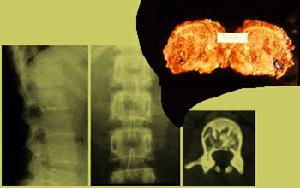

胰高糖素瘤起病緩慢,病程較長,即使有腫瘤轉移,平均病程約10~12年。以中年以上女性多見。診斷依據血漿胰高糖素水平明顯升高,B超或CT證實腫瘤的存在。須與引起胰高糖素增高的其他疾病鑑別,如糖尿病、胰腺炎及其他應急狀態。